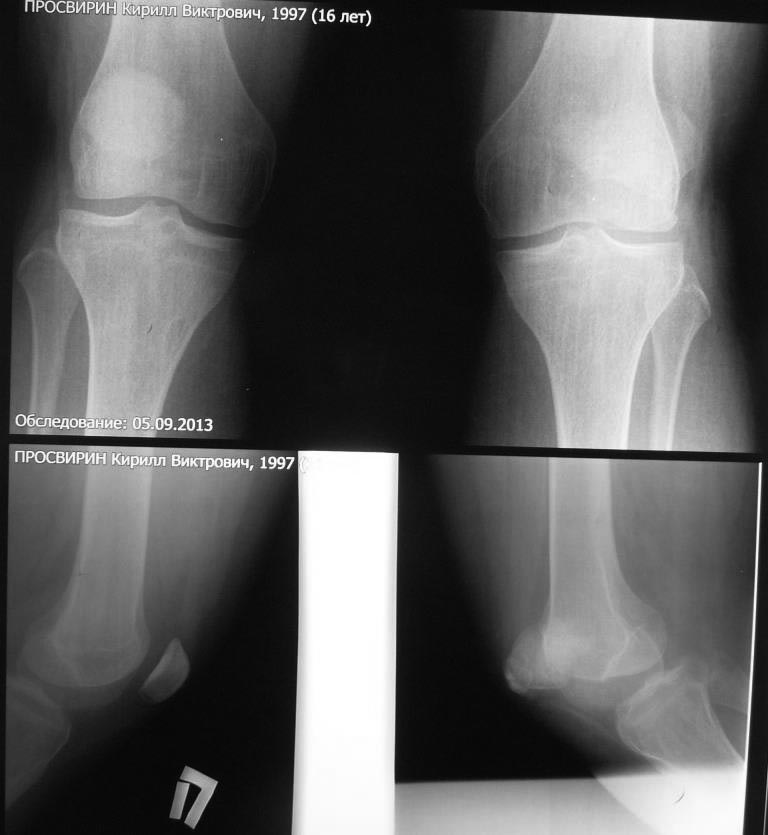

В травматологическом отелеении находится 16 летний юноша с пателло-феморальным артрозом, вторичной деформацией мыщелка бедра и надколенника.

Крупный ребёнок 16 лет. Избыточный вес. Не заинтересован в физических нагрузках. Обратился с жалобами на боли в левом коленном суставе при ходьбе. В 2011 году находился на стационарном лечении в нашей кинике по поводу застарелого перелома внутреннего края левого надколенника с разрывом капсулы сустава, хондромаляции наружного мыщелка бедра и гемартроза. За год до госпитализации перенёс двукратный спонтанный вывих левого надколенника. В отделении (март 2011 года) выполнена артроскопия, санация гиалинового хряща наружного мыщелка. Артропластика по Кемпбеллу. Рентгенограммы той поры не сохранились. Через 2 месяца после оперативного лечения ребёнок находился в отделении по поводу послеоперационной-посттравматической разгибательной контрактуры коленного сустава.

При осмотре: Походка не изменена. Вальгусная деформация коленных суставов: справа – 12, слева 15. Движения в коленных суставах в полном объёме. Выпот не определяется. Наружная ротация левой стопы 15-20 градусов. Левый надколенник латеролизован. При сгибании левого коленного сустава происходит наружная дислокация надколенника.

Фото больного и результаты рентгенологического обследования прилагаем (будут выкладываться последовательно).

Исходя из жалоб и результатов обследования, нами рассматривается следующий вариант хирургической помощи больному. Надмыщелковая остеотомия бедра, выполнение 15 градусов внутренней ротации дистального сегмента, его варизирующее отклонение на 15 град. до исправления вальгуса (анатомической оси конечности ). Очень сомневаемся в отношении вмешательства на поддерживающем аппарате надколенника. Мнения разделились: сделать латеральный релиз , либо не трогать совсем. Делать ли дупликатуру медиального отдела капсулы?

Вызывает опасения неконгруентность суставной поверхности надколенника. Рассматриваем вариант V-образной остеотомии надколенника. Следует ли «подгонять» такой надколенник по мыщелку или оставить в надежде на постепенную перестройку. Как одна из ожидаемых проблем после выполнения вмешательства – резкое ограничение сгибания, так как в настоящее время надколенник «уезжает» с мыщелка при сгибании – что, скорее всего, вызвало укорочение квадрицепса и собственной связки надколенника. Может ли появиться необходимость вмешательства на собственной связке и бугристости одномоментно?